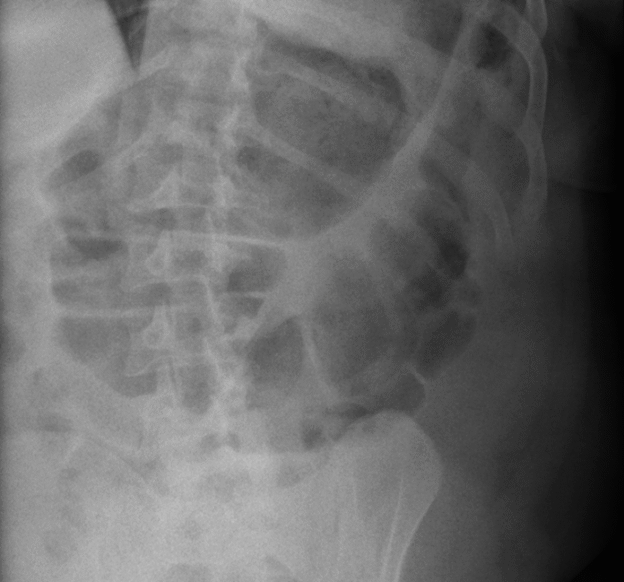

55-year-old man with abdominal pain

A 55-year-old man presented with abdominal pain.